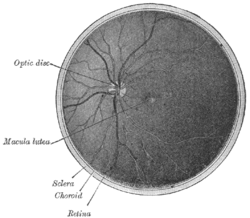

The optic disc or optic nerve head is the point of exit for ganglion cell axons leaving the eye. Because there are no rods or cones overlying the optic disc, it corresponds to a small physiological blind spot in each eye.

The ganglion cell axons form the optic nerve after they leave the eye. The optic disc represents the beginning of the optic nerve and is the point where the axons of retinal ganglion cells come together. The optic disc is also the entry point for the major blood vessels that supply the retina.[1] The optic disc in a normal human eye carries from 1-1.2 million neurons from the eye towards the brain.

Anatomy

The optic disc is placed 3 to 4 mm to the nasal side of the fovea. It is a vertical oval, with average dimensions of 1.76mm horizontally by 1.92mm vertically.[2] There is a central depression, of variable size, called the optic cup.